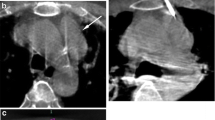

The use of CBCT in the visualization and localization of hepatic lesions at the time of intervention is crucial for effective intra-arterial therapy in seeing and reaching the lesion and in assessing response [21]. DSA can provide excellent vascular visualization but it has less sensitivity for tumor detection than CT or CBCT due to its low soft-tissue contrast and 2D projection nature [15, 23–28]. This can also limit the identification of feeding vessels to tumor [29–31]. CBCT with its 3D nature, soft-tissue contrast, and especially coupled with post-processing software is superior to DSA in lesion detection and tumor feeding vessel identification [23, 30–37]. Figure 3 shows multimodality matching of a target HCC lesion in the pre-TACE MR with post-DEB delivery CBCT, confirming delivery of the DEB-contrast medium mixture. The intra-procedural DSA shows only a blush of the lesion. The role of CBCT can also be seen in therapy response assessment, in particular for Lipiodol deposition (Fig. 4) [27, 38–41] or for marginal contrast retention with DEB, which is associated with successful treatment outcomes 1 month post-DEB [27].

74-year-old male with HCC based on imaging findings and elevated AFP level. NASH and cirrhosis etiology. Child-Pugh class B, BCLC B, ECOG 0. The arrow indicates the target lesion that was treated with DEBs. Note the matching of the lesion in the pre-TACE MR with the intra-procedural CBCT post-DEB delivery

55-year-old male patient with biopsy proven HCC. Hepatitis C and cirrhosis etiology. Child-Pugh class A, BCLC B, ECOG 0. The arrows indicate the lesions targeted with delivery of Lipiodol. Note that the lesion depiction on the pre- and intra-procedural imaging matches with the post-TACE imaging, and especially with the hypoenhancement 1 month post-TA

A more recent development is the Dual Phase CBCT, where a bi-phasic CBCT is acquired using a single contrast injection. Dual phase has increased tumor detection versus single-phase CBCT alone and is comparable to the gold standard of contrast-enhanced MDCT and MRI in lesion detection and in predicting therapy response [28, 42, 43]. With these highlights of CBCT in lesion detection, tumor feeding vessel identification, and therapy assessment, the addition of CBCT along with DSA can prolong patient survival [44].